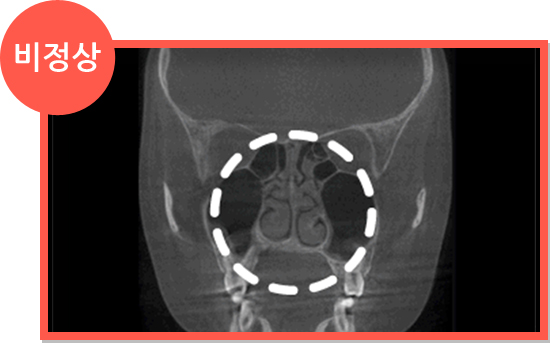

비염 CT 정상 소견 비염 CT 비정상 소견